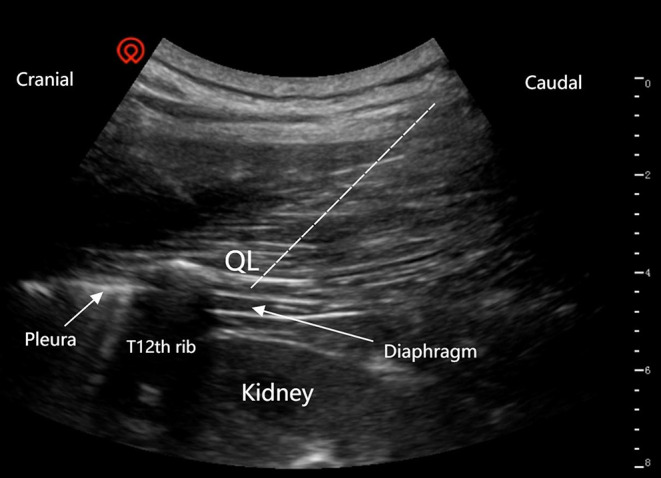

Purpose: Quadratus lumborum block at the lateral supra-arcuate ligament (QLB-LSAL) has demonstrated efficacy in postoperative pain management for laparoscopic nephrectomy patients. Liposomal bupivacaine, a novel sustained-release local anesthetic, provides analgesia lasting up to 72 hours. However, its analgesic effect in QLB-LSAL remains undetermined. This randomized controlled trial aimed to compare the postoperative analgesic efficacy of liposomal bupivacaine versus bupivacaine hydrochloride in patients receiving QLB-LSAL after laparoscopic nephrectomy.

Patients and methods: A total of 116 patients were scheduled to undergo elective laparoscopic nephrectomy under general anesthesia. Patients were randomly assigned to two groups in a 1:1 ratio. The liposomal bupivacaine group (n = 53) received a mixture of 10 mL of liposomal bupivacaine (133mg) and 10 mL of normal saline, totaling 20 mL, while the bupivacaine hydrochloride group (n = 53) received 20 mL of 0.375% bupivacaine hydrochloride. Post-surgical patient-controlled sufentanil analgesia was provided. The primary outcome was total morphine equivalent consumption within the first 48 hours postoperatively.